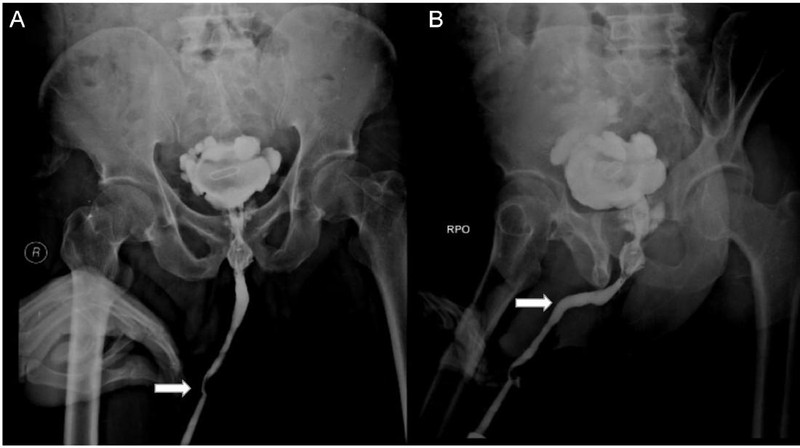

Seorang remaja laki-laki berusia 15 tahun di Inggris dilarikan ke rumah sakit gegara ada kabel USB tersangkut di dalam penisnya. Awalnya, remaja tersebut berupaya mengukur bagian dalam penisnya menggunakan kabel. Kasus tersebut diterbitkan di Urology Case Report pada 2021. (Foto: Calum Grant/ Urology Case Reports).